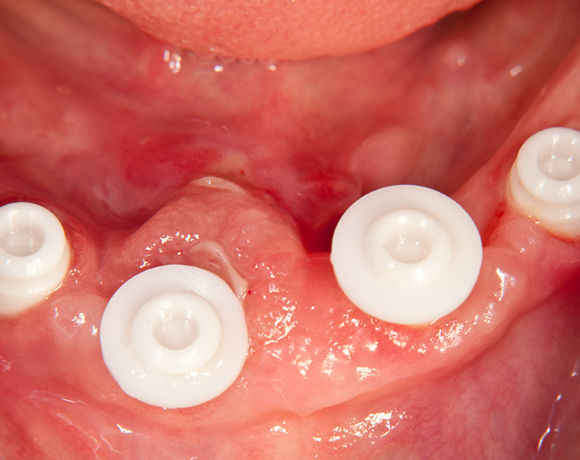

Bild 03: Aufsetzen der Montageaufsätze

Bild 04: Aufsetzen der Matrizengehäuse